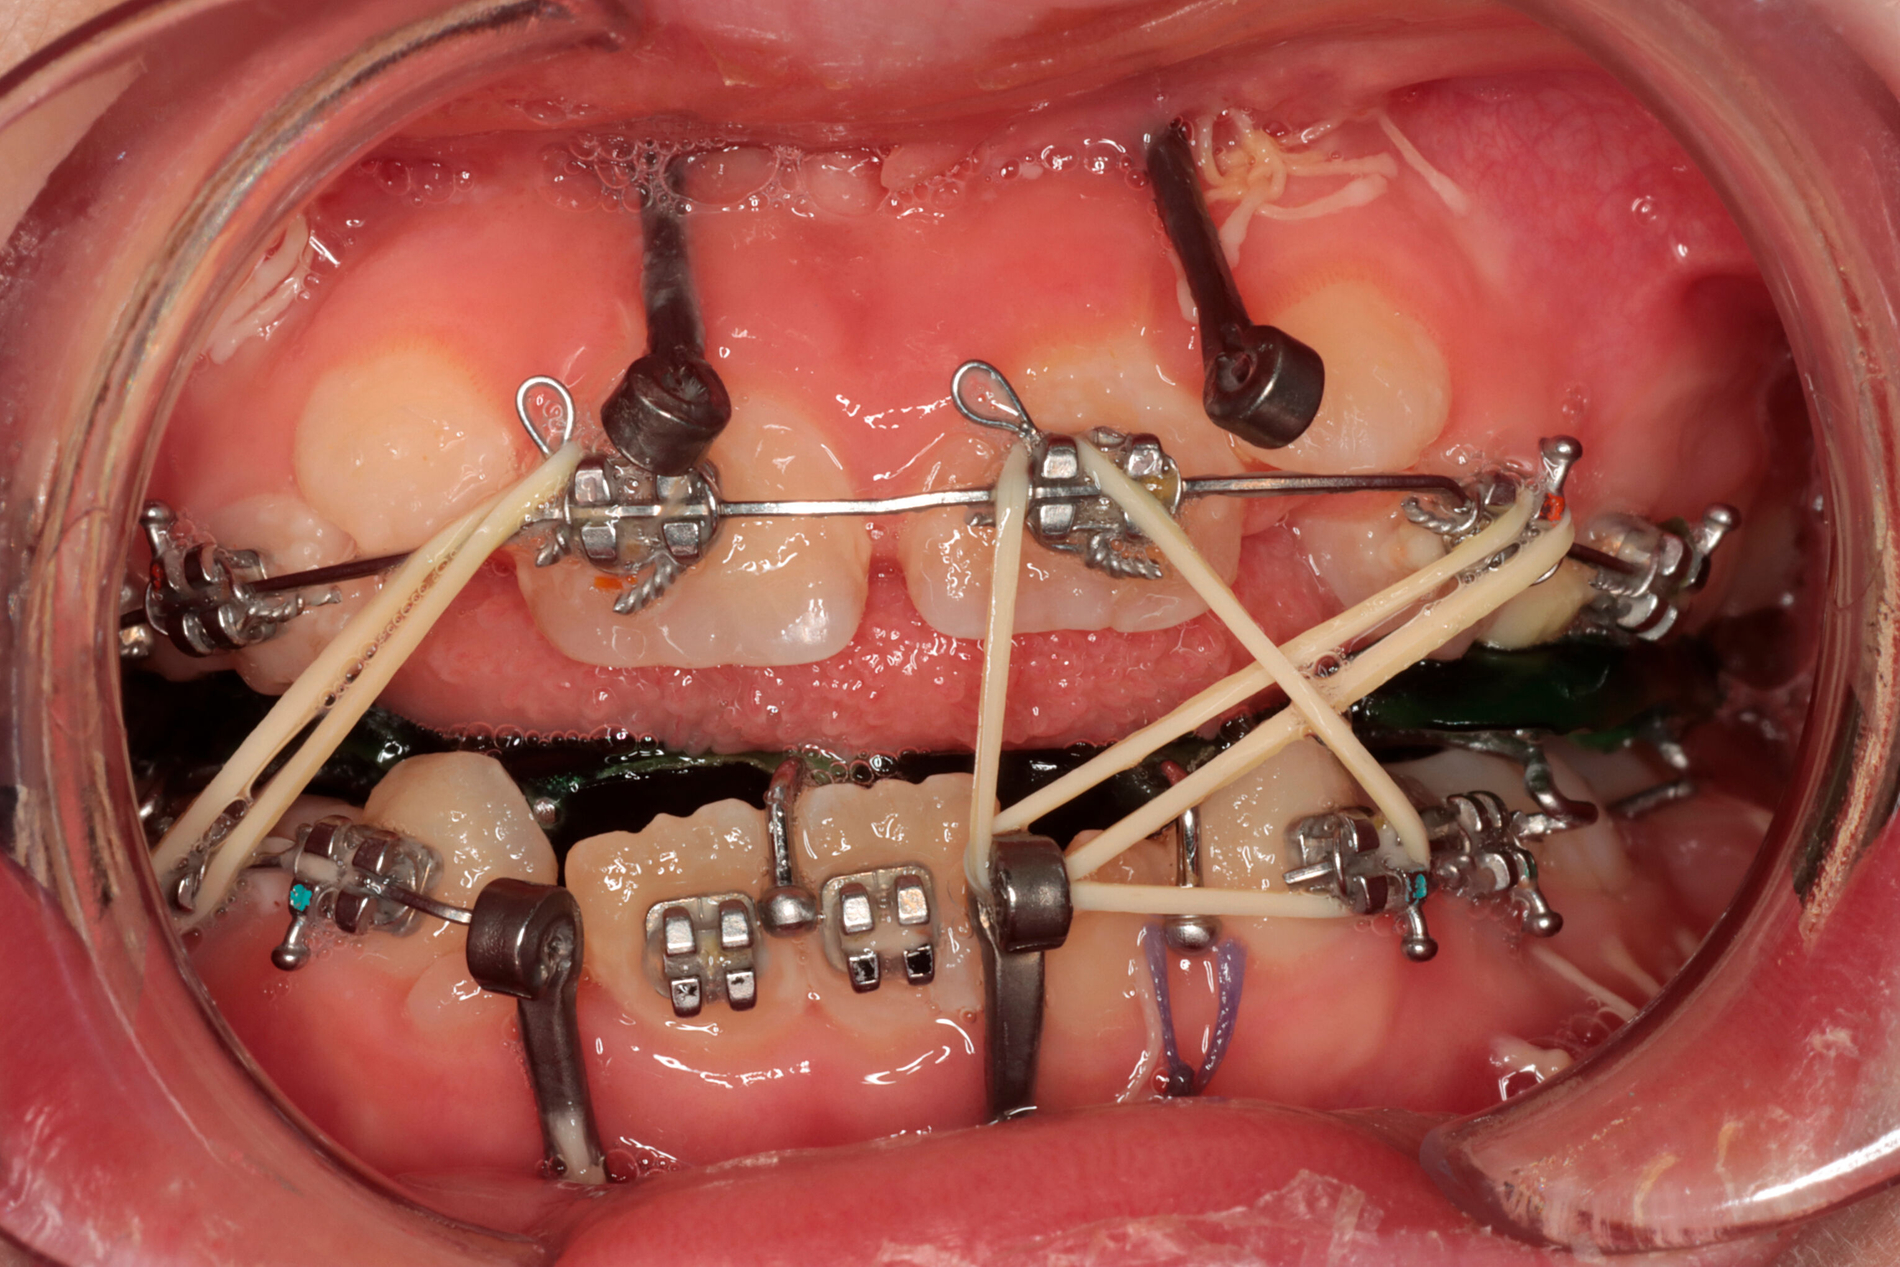

Befürworter der Distraktion argumentieren, dass die in jedem Fall notwendige Umstellungsosteotomie vom vermehrten Knochenangebot der vorangegangenen Distraktion signifikant profitiert, wodurch ein besseres ästhetisches Ergebnis gegenüber der alleinigen bignathen Umstellung erreicht werden kann [Shakir und Bartlett, 2021]. Zu beachten ist die Gefahr einer Kondylusresorption des häufig nur rudimentär ausgebildeten Kiefergelenks als Folge der hohen Druckbelastung bei gleichzeitig insuffizienter Abstützung während einer Ramusdistraktion. Dieses Risiko kann und sollte durch die Eingliederung einer kieferorthopädischen Aufbiss-Apparatur und von anterioren Gummizügen zur Druckentlastung der Gelenkregion verringert werden (Abbildung 6).

Auch für die hemifaziale Mikrosomie könnte die gleichzeitige laterale Distraktion des Unter- und Oberkiefers in Okklusion eine zielführende Option darstellen, da über die Okklusion und den Distraktor des Oberkiefers die vertikalen Kräfte der Ramusdistraktion auf das stabile Jochbein übertragen werden und somit die Resorptionsgefahr des Kondylus sinkt bei gleichzeitiger Gewährleistung der Okklusion [Lu et al., 2016].